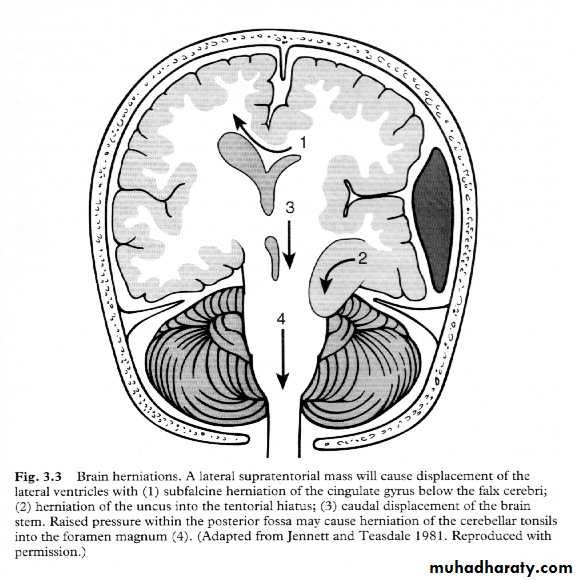

7. Cerebral Herniation

a. Subfalcine Herniation

b. Uncal Herniation

c. Tentorial Herniation

d. Tonsillar Herniation

a. Transtentorial Herniation

b. Foramen magnum herniation

c. Subfalcine Herniation